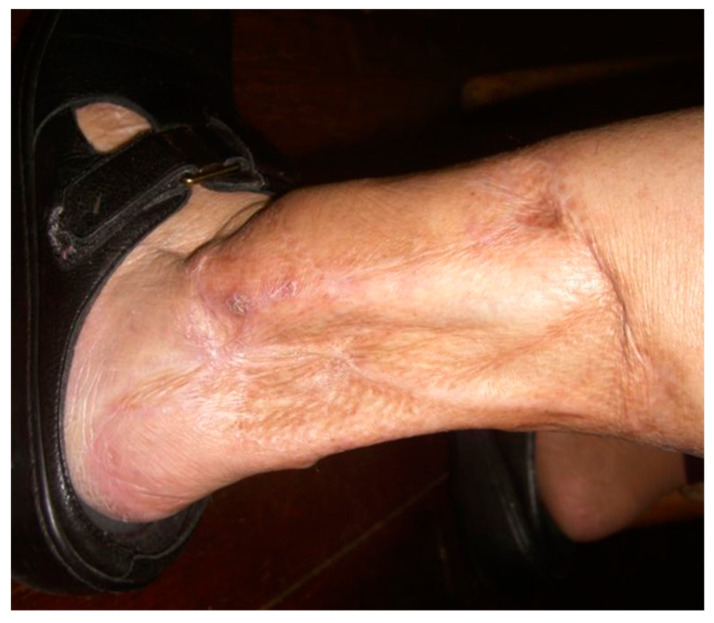

Most wounds heal uneventfully within 90 days of injury progressing through the three phases of wound healing. However, in 1–2% of wounds, the process lingers at the inflammatory phase and fails to move beyond that. The result is an open, chronic wound. There are many reasons for wound healing to go awry, often delayed as in chronic wounds but at times excessive, as in hypertrophic scars and keloids. For chronic wounds, it is important to examine the “whole” patient before examining the “hole” in the patient (Figure 4). Causal relationships in biology and medicine are often hard to establish definitively, due to their multifactorial and context-dependent nature. These are the defining characteristics of complex adaptive systems [ref. 46,ref. 47]. It remains always true that insufficient nutrient and oxygen delivery to the tissue will result in cell death and tissue breakdown, as life occurs far from thermodynamic equilibrium. Since the vascular system supplies all the required substrates (lower entropy) and removes all the wastes (higher entropy), the compromise of this mass transfer apparatus is always a part of the chronic wound. Such compromise may be at the macrovascular level or, as in the case of pressure ulcers, at the level of the capillaries.

Because of all the above, diabetic wound healing does not progress normally and tends to remain in a chronic inflammatory state. Combining the micro- and macro-level abnormalities, the lifetime risk of developing foot ulcers in diabetic patients is one in three, with many eventually requiring amputations [ref. 69].